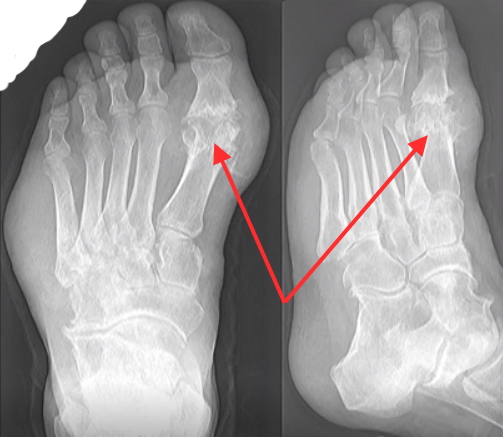

Существенным препятствием для изучения ОА стопы было отсутствие специальной системы оценки стопы для определения рентгенологического ОА стопы. В большинстве (90%) исследований, включенных в недавний систематический обзор, использовалась система оценки K&L, которая широко используется для оценки рентгенографического ОА на различных участках суставов. 20,21 Хотя общая система, такая как K&L, имеет то преимущество, что позволяет сравнивать распространенность и особенности ОА на разных участках, ее критиковали за то, что она в значительной степени полагалась на наличие остеофита и за оценку характеристик ОА в таком Путь, который предполагает образование остеофитов, хронологически предшествует сужению суставной щели и субхондральному склерозу в патогенезе ОА. 22–24 Сообщается, что еще одним недостатком является непоследовательная интерпретация и применение оценок между исследованиями. 11 Таким образом, важным недавним достижением стало появление специфичного для стопы рентгенологического атласа и системы оценки для оценки рентгенологических характеристик (остеофитов и сужения суставной щели) ОА стопы. 25 В этом атласе оцениваются особенности ОА в пяти различных суставах стопы: первом MTP, первом и втором клино-метатарзальном (CMT), ладьевидном первом клиновидном (NC) и таранно-ладьевидном (TN) суставах (). Эти суставы были выбраны, так как они легко визуализируются на дорзоплантарных и боковых проекциях и, по мнению авторов, являются суставами стопы, наиболее часто поражаемыми ОА.Следовательно, этот атлас не предоставляет средств для оценки остеоартрита, возникающего в боковом столбике или в задней части стопы. Однако он имеет преимущества, состоящие в том, что остеофиты и сужение суставной щели оцениваются отдельно (и), а также требуются дорзо-подошвенные и боковые виды с опорой на вес, что связано с наблюдением, что в существующих исследованиях часто не указывается, были ли рентгенограммы несущими или были получены только одиночные рентгенологические снимки. Посмотреть. 9 Получение более одного изображения позволяет лучше учитывать особенности отдельных суставов.Например, остеофиты в суставе TN чаще всего визуализируются на боковой проекции, в то время как сужение суставной щели во втором суставе CMT легче оценивается на дорзоплантарной проекции, чем на боковой проекции (). Остеофиты (отсутствуют = 0, небольшие = 1, средние = 2, тяжелые = 3) и сужение суставной щели (отсутствуют = 0, определенные = 1, тяжелые = 2, сращение суставов = 3) оцениваются отдельно по шкале от 0 до 3 баллов по вид спереди и сбоку. Рентгенологический ОА присутствует в конкретном суставе, если есть минимум 2 балла для остеофита или сужения суставной щели на дорзоплантарной или боковой проекции.Внутриэкспертная надежность была от умеренной до отличной (взвешенная κ 0,45–0,95), тогда как надежность между экспертами была ниже (взвешенная κ 0,13–0,87), что согласуется с исследованиями надежности в области бедра и колена. 26

Рентгенограмма остеоартроза первого плюснефалангового сустава.Открытая стрелка указывает на сужение суставной щели, а закрашенная стрелка указывает на остеофит.

Рентгенологические признаки остеоартроза среднего отдела стопы. Стрелки указывают на сужение первой клинеометатарзальной и второй клинеометатарзальной суставной щели.